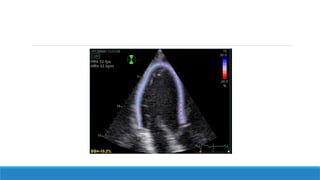

♣ Acquisition des images en 2D sur un cycle cardiaque

♣ ECG ++++

♣ Cadence image 50 à 80 MHz

♣ Traitement directement sur l’appareil ou post-traitement sur l’echopack

♣ Limites: Nécessité d’une bonne echogénicité +++ Rythme régulier

♣ Pour le strain global longitudinal: 3 coupes apicales: 3 cavités, 4C et 2C